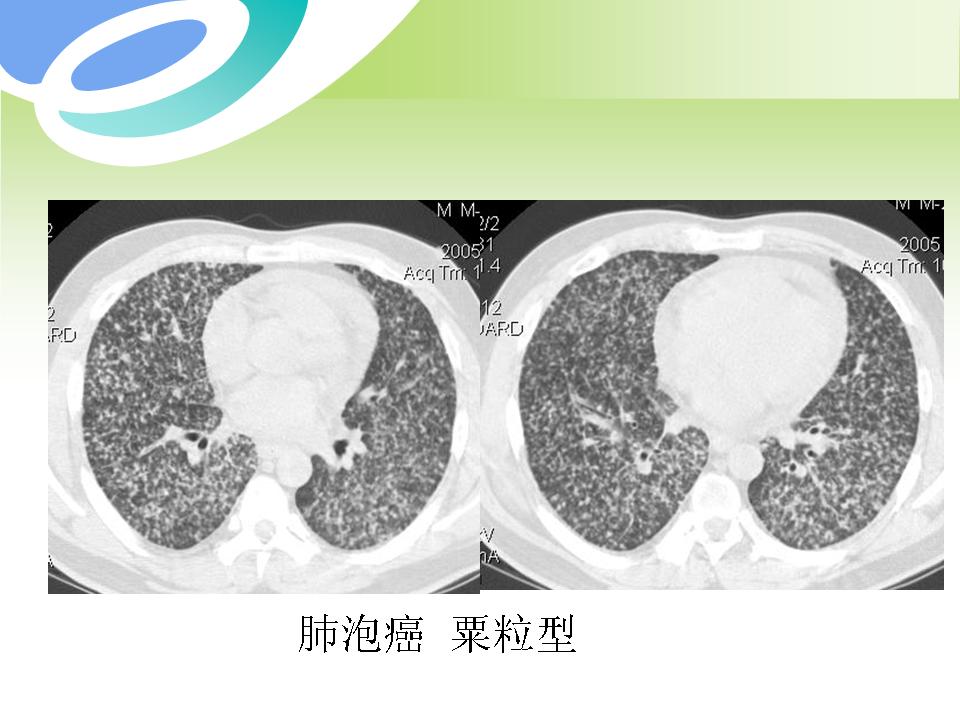

肺部病变的CT基本征象